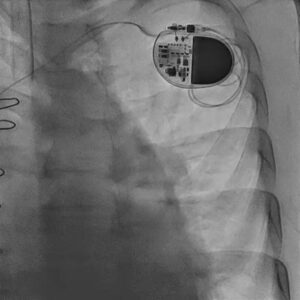

Figure 4. Post-procedural chest fluoroscopic image showing the implanted permanent pacemaker system.

Post-procedural echocardiography confirmed a well-seated mitral valve-in-valve prosthesis with clear haemodynamic improvement. The mitral valve area increased to approximately 1.3 to 1.4 cm², and residual transvalvular gradients were low. Biventricular systolic function remained preserved.

From a clinical standpoint, this represented successful restoration of mitral valve performance in a patient who had presented in heart failure with a critically stenosed prosthesis. The permanent pacemaker also ensured electrical stability after complete heart block, completing the second major component of his treatment.

Together, these outcomes underscore how coordinated transcatheter therapy and pacing intervention can change the trajectory of care in elderly high-risk patients.